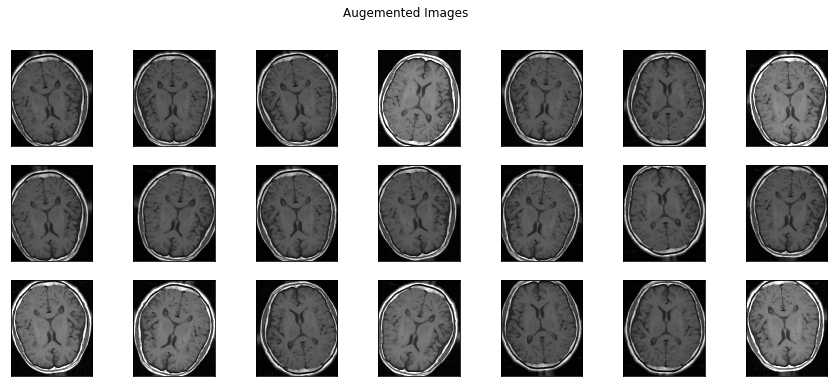

今回のデータセットの画像は100〜200枚しかなかったので、データを水増しします。

水増しすると悪いことをやっているようですが、機械学習の世界では良い行いとされています。

水増しの手法は色々あって、一般的には下記のようなことが行われます。

- 画像を回転

- 画像を上下左右にずらす(はみ出しても良し)

- 左右上下反転

- 明るさを変える

以下は水増しした画像です。微妙に違う画像が並んでいます。

水増しを行う時の注意点としては、水増しをしすぎるとたくさんの似たような画像から学習をすることになってしまうので、過学習が起きやすいということです。

なので水増しはほどほどにしておきましょう。